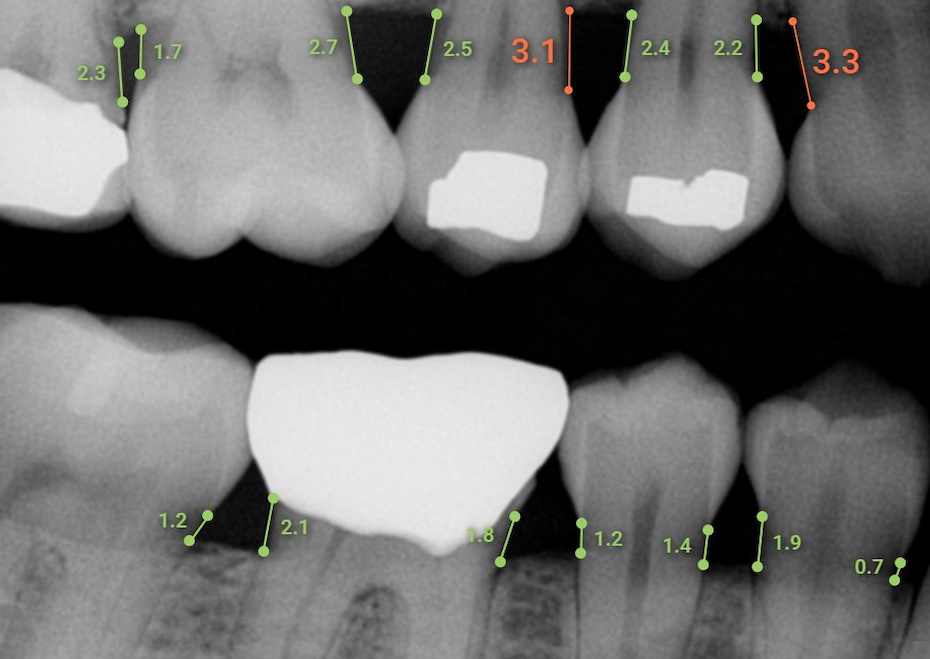

The clearance by the FDA will enable Overjet to market and sell the AI product directly to dental practices. The software supports dental professionals in measuring mesial and distal bone levels in bitewing and periapical radiographs for the diagnosis and treatment planning of periodontal disease. The condition affects an estimated 46 percent of U.S. adults, including 8.9 percent who have severe periodontitis, according to the manufacturer. Left untreated, periodontitis can lead to tooth loss and painful chewing.

In clinical performance testing, Overjet Dental Assist demonstrated automated measurement capabilities comparable to a team of highly skilled dentists. Overjet had 3 experienced dentists independently measure bone levels on dental radiographs using a measuring tool. These measurements were then further adjudicated by an oral radiologist to establish an official consensus ground truth. Overjet’s AI-powered Dental Assist measurements were then compared against this dentist consensus and had an average difference of only 0.3mm.

“We’re seeing dental AI software perform at the level of a team of trained dentists with accuracy closer than the width of a needle,” says Chris Balaban, DMD, Clinical Director for Overjet. “These tools unlock the ability to track the progression of disease over time for each tooth and make the case for evidence-based treatment, supported by unbiased software and clear visuals for patients.”